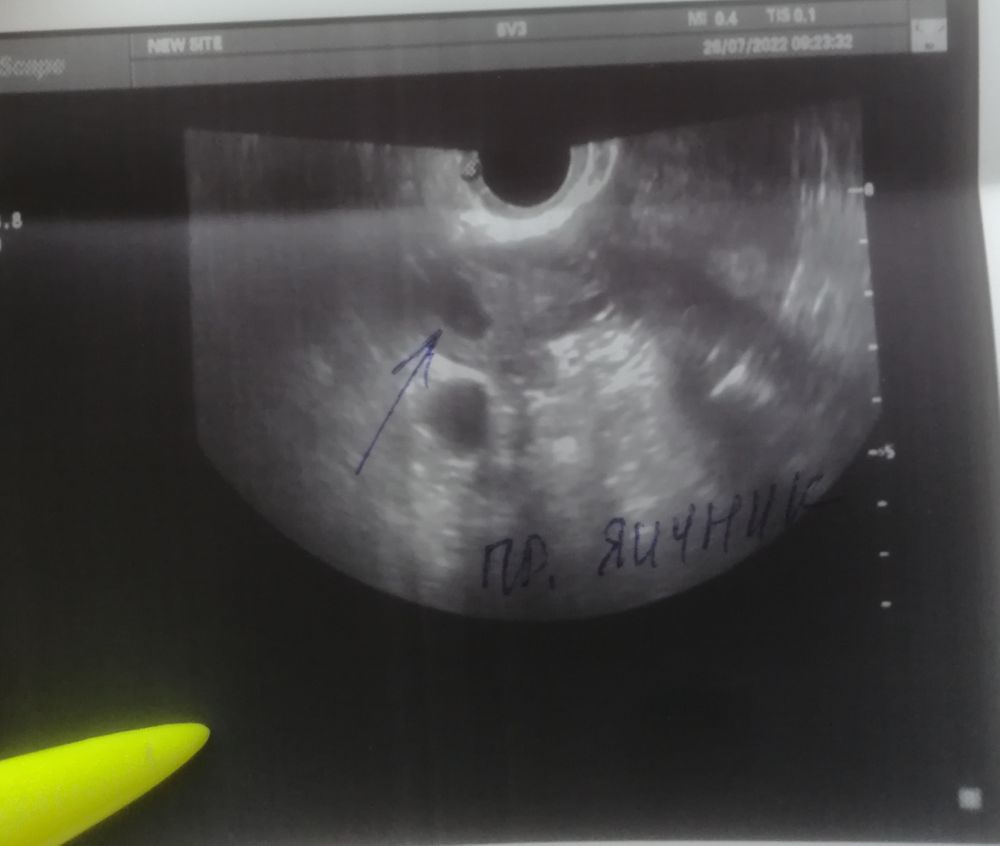

Добрый день девочки. Вообщем ситуация такая, сегодня 20 дц, цикл 28 дней, обычно болит грудь после овуляции всегда, но не в этом месяце, я решила сходить на узи т.к думала что цикл ановуляторный, но узи это не подтвердило и в итоге сказали, что либо

была овуляция двойная и два жёлтых тела, либо одно жт и один дф и овуляция ещё будет. Цикл стабильный, задержек не бывает, максимум 1 день. И как при 28 дневном цикле возможна овуляция на 20 дц, а то и позже, если предположить что это всё таки дф и он 16 мм. Может кто разбирается, что на фото всё таки? Заранее всем спасибо. 🙏